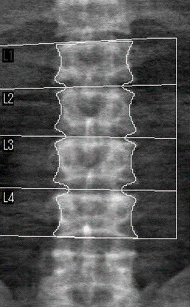

骨量測定(DEXA法)

DEXA(Dual-energy X-ray absorptiometry)とは,日本骨粗鬆学会ガイドラインや世界中の骨粗鬆症ガイドラインで基準測定器として定められているX線骨密度測定装置です。

骨量(骨塩量・骨密度)を測定する検査で,骨粗鬆症の診断や治療効果の判定,投薬治療による骨量変化の観察に用いられます。主に転倒などによる骨折が起こると重症化しやすい腰椎,大腿骨頸部の測定を行っています。

腰椎骨量測定